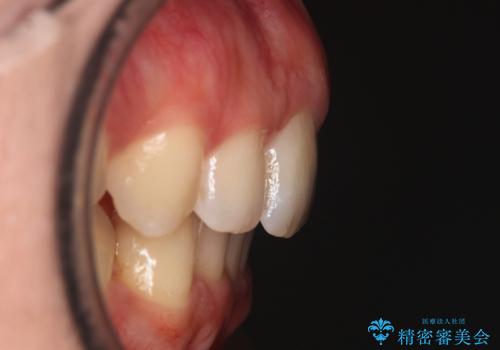

右側臼歯部の咬合改善のために、臼歯部のみ部分的なワイヤー矯正を行い、咬合改善がみられてからインビザラインにて全体的な矯正を行なっていく治療計画を立てました。

噛み合わせをよくするために、ワイヤー矯正とインビザライン矯正のどちらの期間も必要な箇所にゴム掛けを行いながら治療を行いました。

ゴム掛けを頑張っていただいたので、噛みあわせも改善され綺麗な歯並びになりました。